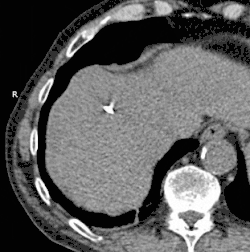

GIF animé montrant par scanner une cryoablation réalisée sur le foie. Le processus dure environ 30 minutes.